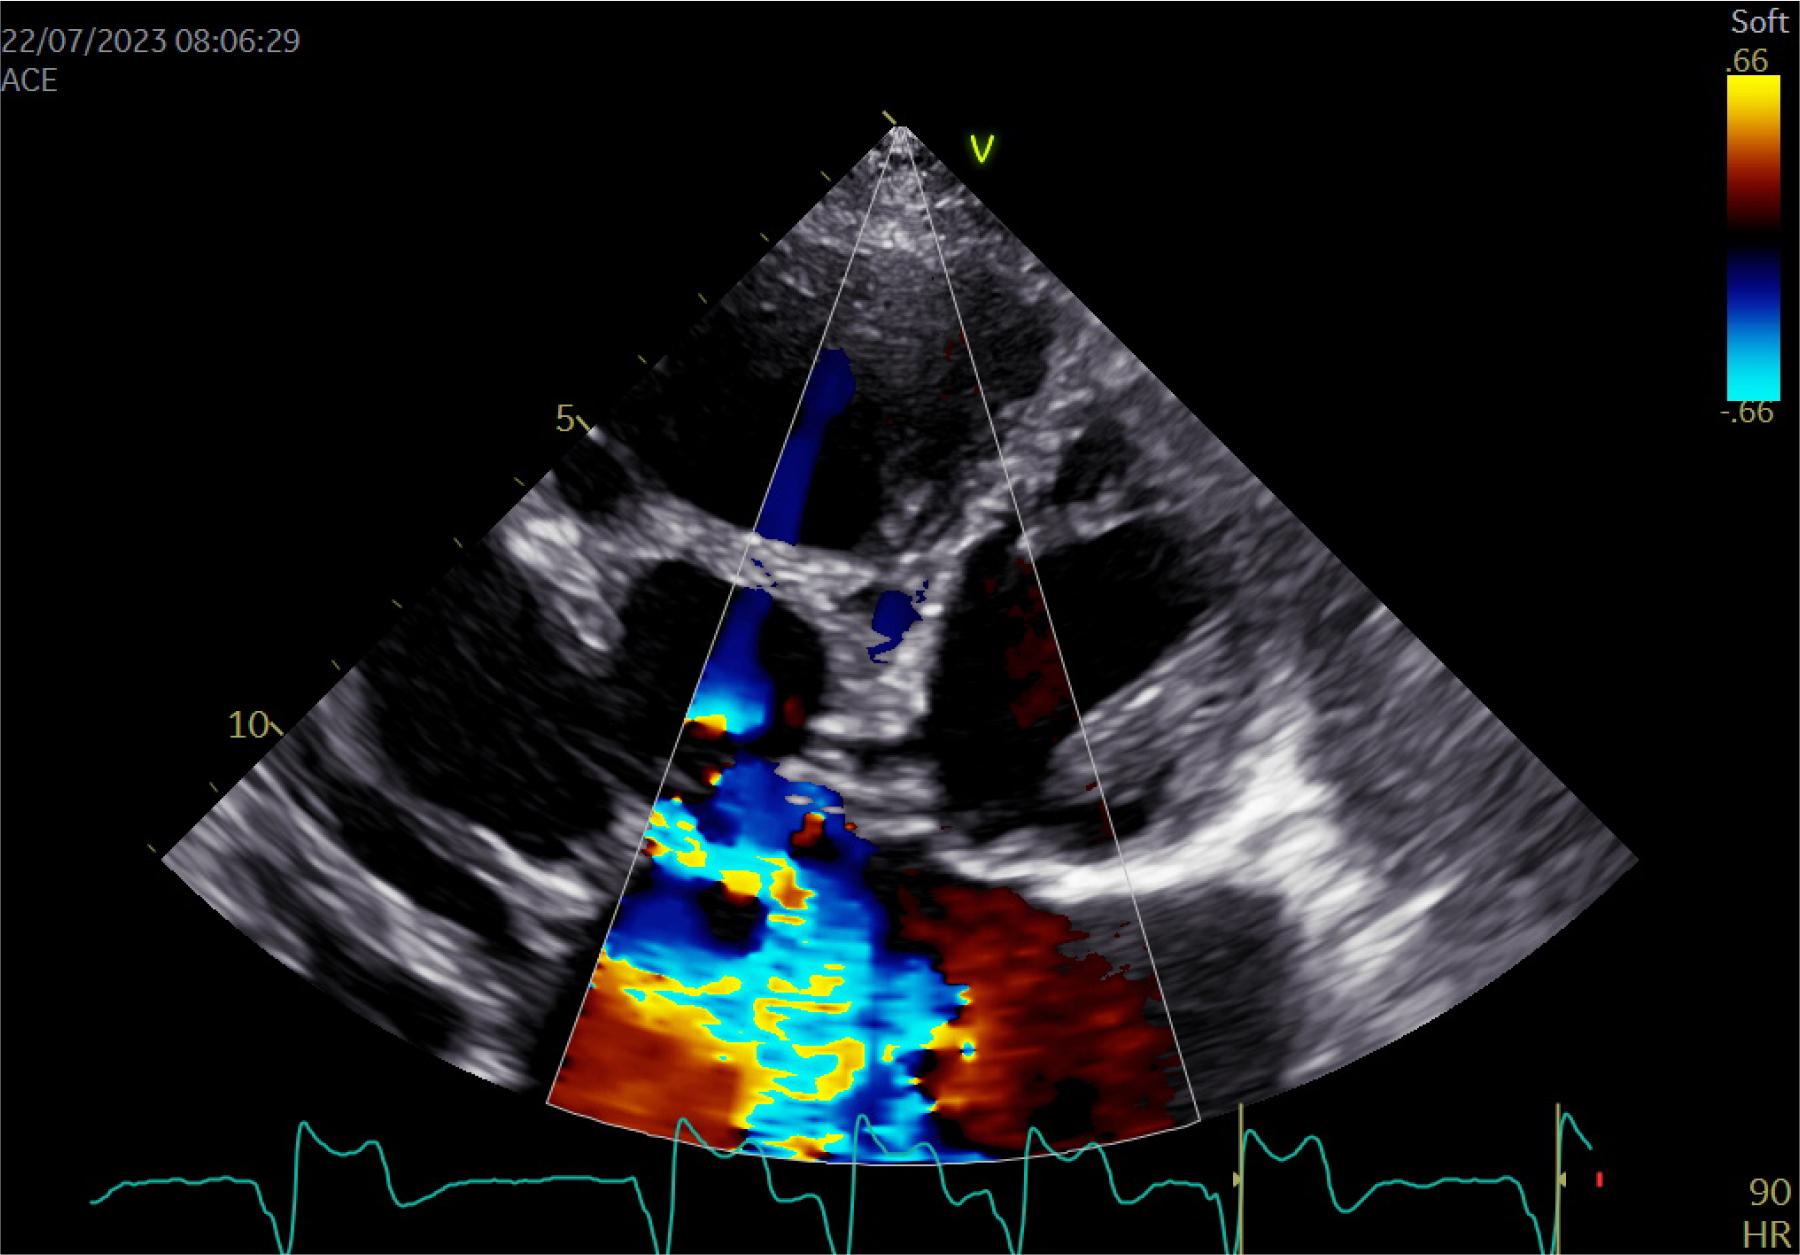

A more detailed echocardiographic evaluation was repeated and revealed a single atrium with a volume of 530 ml, severe mitral regurgitation, severe tricuspid regurgitation, perimembranous VSD with bidirectional flow on Doppler interrogation, left ventricular (LV) end-diastolic volume of 92 mL and end-systolic volume of 33 mL, LV ejection fraction of 60%, right ventricular (RV) basal/longitudinal/medium diameters of 71/89/80 mm, RV longitudinal systolic dysfunction (suggested by the tricuspid annulus plane systolic excursion of 11 mm), estimated pulmonary artery systolic pressure of 92 mmHg, Qp:Qs=3.89, dilated inferior vena cava, mild pulmonary regurgitation, and moderate pericardial effusion (Figure 2–3, video 1-2).

Transthoracic echocardiography modified apical 4-chambers view, color doppler: severe tricuspid regurgitation.